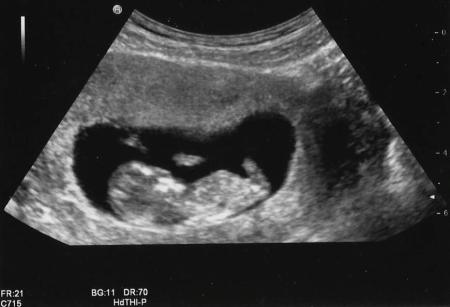

At 12 weeks I had a heavy bleed, thin blood poured out like I was peeing myself, I don’t have a clue how much I lost but it seemed an awful lot. It was all over in 10 minutes or so though. This was at midnight on a Saturday, I rushed to out of hours doctors, already sure I was having a miscarriage, but they booked me in for an early scan at the Early Pregnancy Unit first thing on the Monday. Everything was fine and baby had a strong heartbeat. It was such a relief and I clung to the scan picture I was given like a lifeline.

I went for my 12 week routine scan a week later at what turned out to be 13 weeks and they noted a large clot outside the sac and away from the placenta they assured me I may well bleed again as the clot cleared away but lots of women bleed in pregnancy and they weren’t that worried.

At my 20 week scan which happened to be on mine and my fiancés anniversary we were reassured that everything was perfect, heart was fine, kidneys, spine, they even showed us that her lip was formed perfectly. The clot was still there but it didn’t seem to be affecting anything so no one seemed that worried. She kept her legs crossed though keeping us guessing about her gender! It was the most perfect anniversary present for the both of us. I started to relax thinking that the second half of my pregnancy would be ok, the risky part was over, she was ok and perfectly formed, she just needed to grow now, after all, in 4 weeks she would be viable!